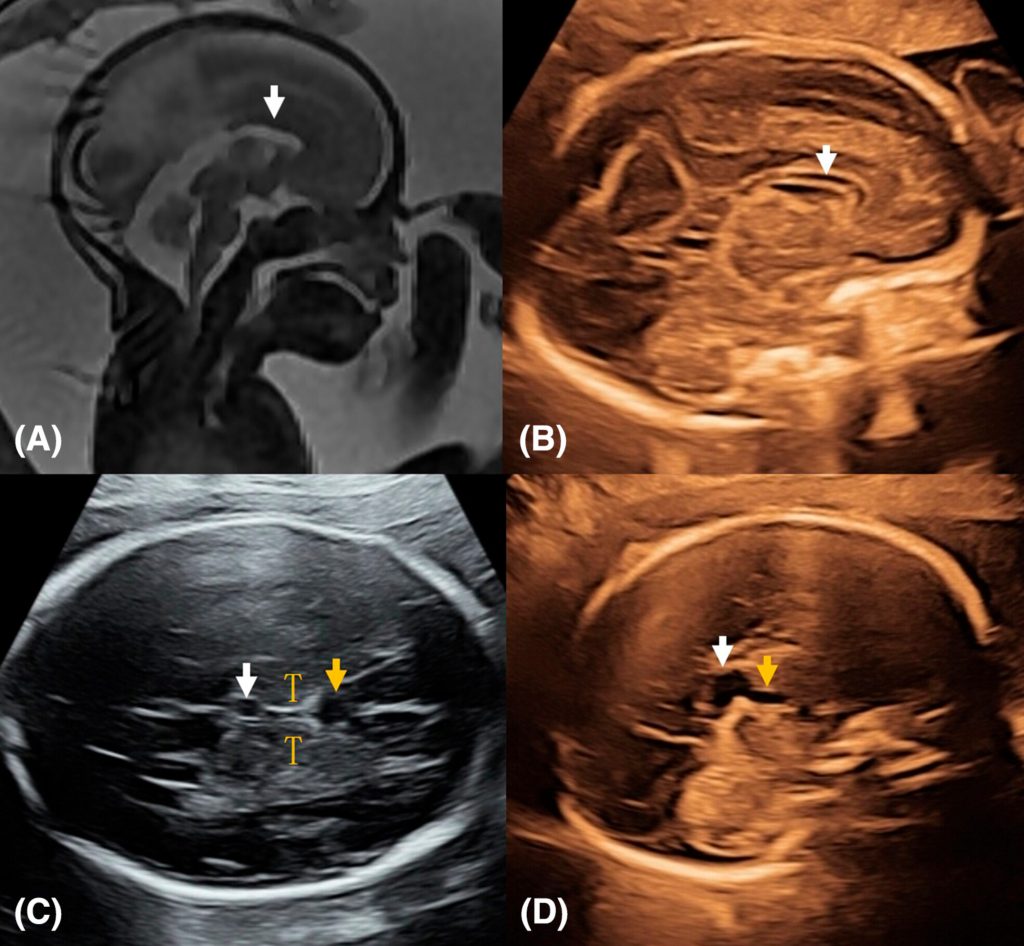

Bất sản thể chai bán phần trên siêu âm được chẩn đoán như thế nào?

Chẩn đoán dựa vào khảo sát mặt phẳng dọc giữa chuẩn. Bác sĩ đánh giá trực tiếp cấu trúc thể chai. Có thể thấy thể chai mỏng hoặc thiếu một đoạn.

Hai dấu hiệu gợi ý thường gặp là:

- Vách trong suốt không rõ

- Giãn não thất nhẹ

Sau đó cần khảo sát thêm mặt phẳng vành. Mục tiêu là loại trừ bất thường cấu trúc não khác.

Không nên kết luận chỉ dựa vào dấu hiệu gián tiếp.

MRI não thai có cần thiết không?

MRI não thai giúp đánh giá chi tiết hơn cấu trúc não. Đặc biệt là vỏ não và chất trắng.

MRI thường được thực hiện sau tuần 20. Giá trị cao hơn sau tuần 26 khi cấu trúc vỏ não phát triển rõ hơn.

Trong các bất thường thể chai, MRI có thể phát hiện thêm tổn thương phối hợp mà siêu âm chưa thấy rõ. Điều này ảnh hưởng trực tiếp đến tư vấn tiên lượng.

Giá trị của MRI phụ thuộc chất lượng siêu âm ban đầu.